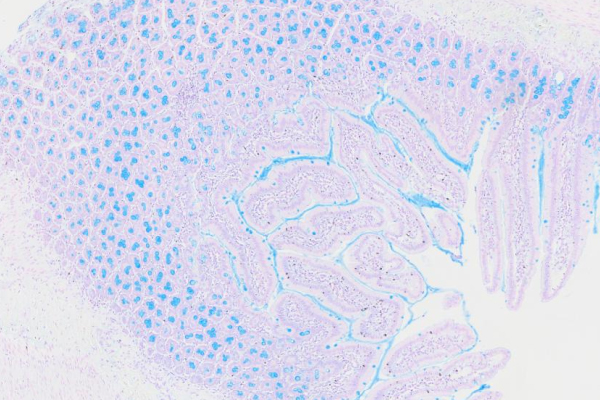

AB-PAS染色

种属:小鼠 | 样本:肠